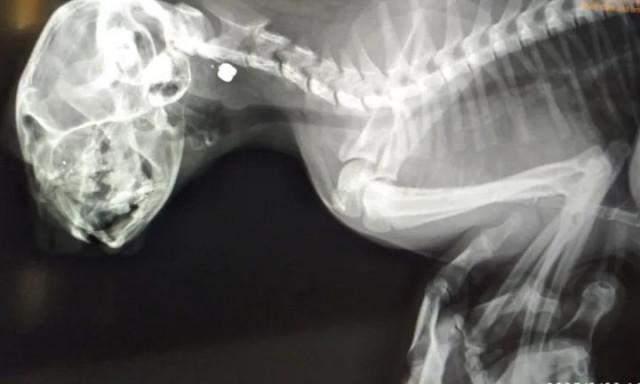

Πάτρα – Κτηνωδία στο Μιντιλόγλι: Αγνωστος πυροβολεί γάτες με αεροβόλο

Τα επαναλαμβανόμενα περιστατικά έχουν προκαλέσει τρόμο και οργή στους κατοίκους της περιοχής

Σοκ προκαλούν οι κτηνωδίες στη Θεσσαλονίκη με θύματα δύο μικρά γατάκια. Βρέθηκαν με σπασμένη γνάθο και χτυπήματα